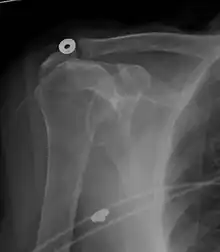

Xray

X-ray projectional radiography cannot directly reveal tears of the rotator cuff, a 'soft tissue', and consequently, normal X-rays cannot exclude a damaged cuff. However, indirect evidence of pathology may be seen in instances where one or more of the tendons have undergone degenerative calcification (calcific tendinitis). The humeral head may migrate upwards (high-riding humeral head) secondary to tears of the infraspinatus, or combined tears of the supraspinatus and infraspinatus.[47] The migration can be measured by the distance between:

- A line crossing the center of a line between the superior and inferior rims of the glenoid articular surface (blue in image).

- The center of a "best-fit" circle positioned over the humeral articular surface (green in image)

Normally, the former is positioned inferiorly to the latter, and a reversal is therefore indicating a rotator cuff tear.[47] Prolonged contact between a high-riding humeral head and the acromion above it, may lead to X-rays findings of wear on the humeral head and acromion and secondary degenerative arthritis of the glenohumeral joint (the ball and socket joint of the shoulder), called cuff arthropathy, may follow.[46] Incidental X-ray findings of bone spurs at the adjacent acromioclavicular joint may show a bone spur growing from the outer edge of the clavicle downwards towards the rotator cuff. Spurs may also be seen on the underside of the acromion, once thought to cause direct fraying of the rotator cuff from contact friction, a concept currently regarded as controversial.